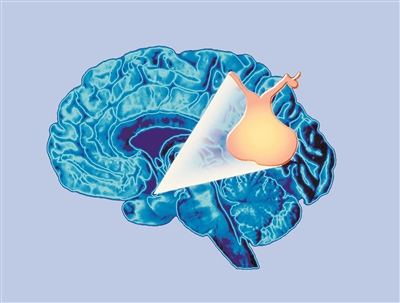

脑垂体示意图。

垂体虽小却负责调控全身激素分泌

“垂体是位于大脑底部的一个小腺体,虽然仅有豌豆大小,却承担着调控全身激素分泌的重要职责。它对我们的生长、代谢、应激反应以及生殖功能有着直接影响。”山西医科大学第一医院内分泌科副主任医师许林鑫在接受科技日报记者采访时说,垂体功能减退症是指垂体前叶或后叶部分或完全功能受损,导致一种或多种垂体激素分泌不足的疾病。

许林鑫告诉记者,脑垂体具有分泌生长激素的作用。因患垂体功能减退症导致身高增加较为罕见。通常情况下,脑垂体功能低下会影响青少年生长激素的正常分泌,可能致使其成年后身高矮小。